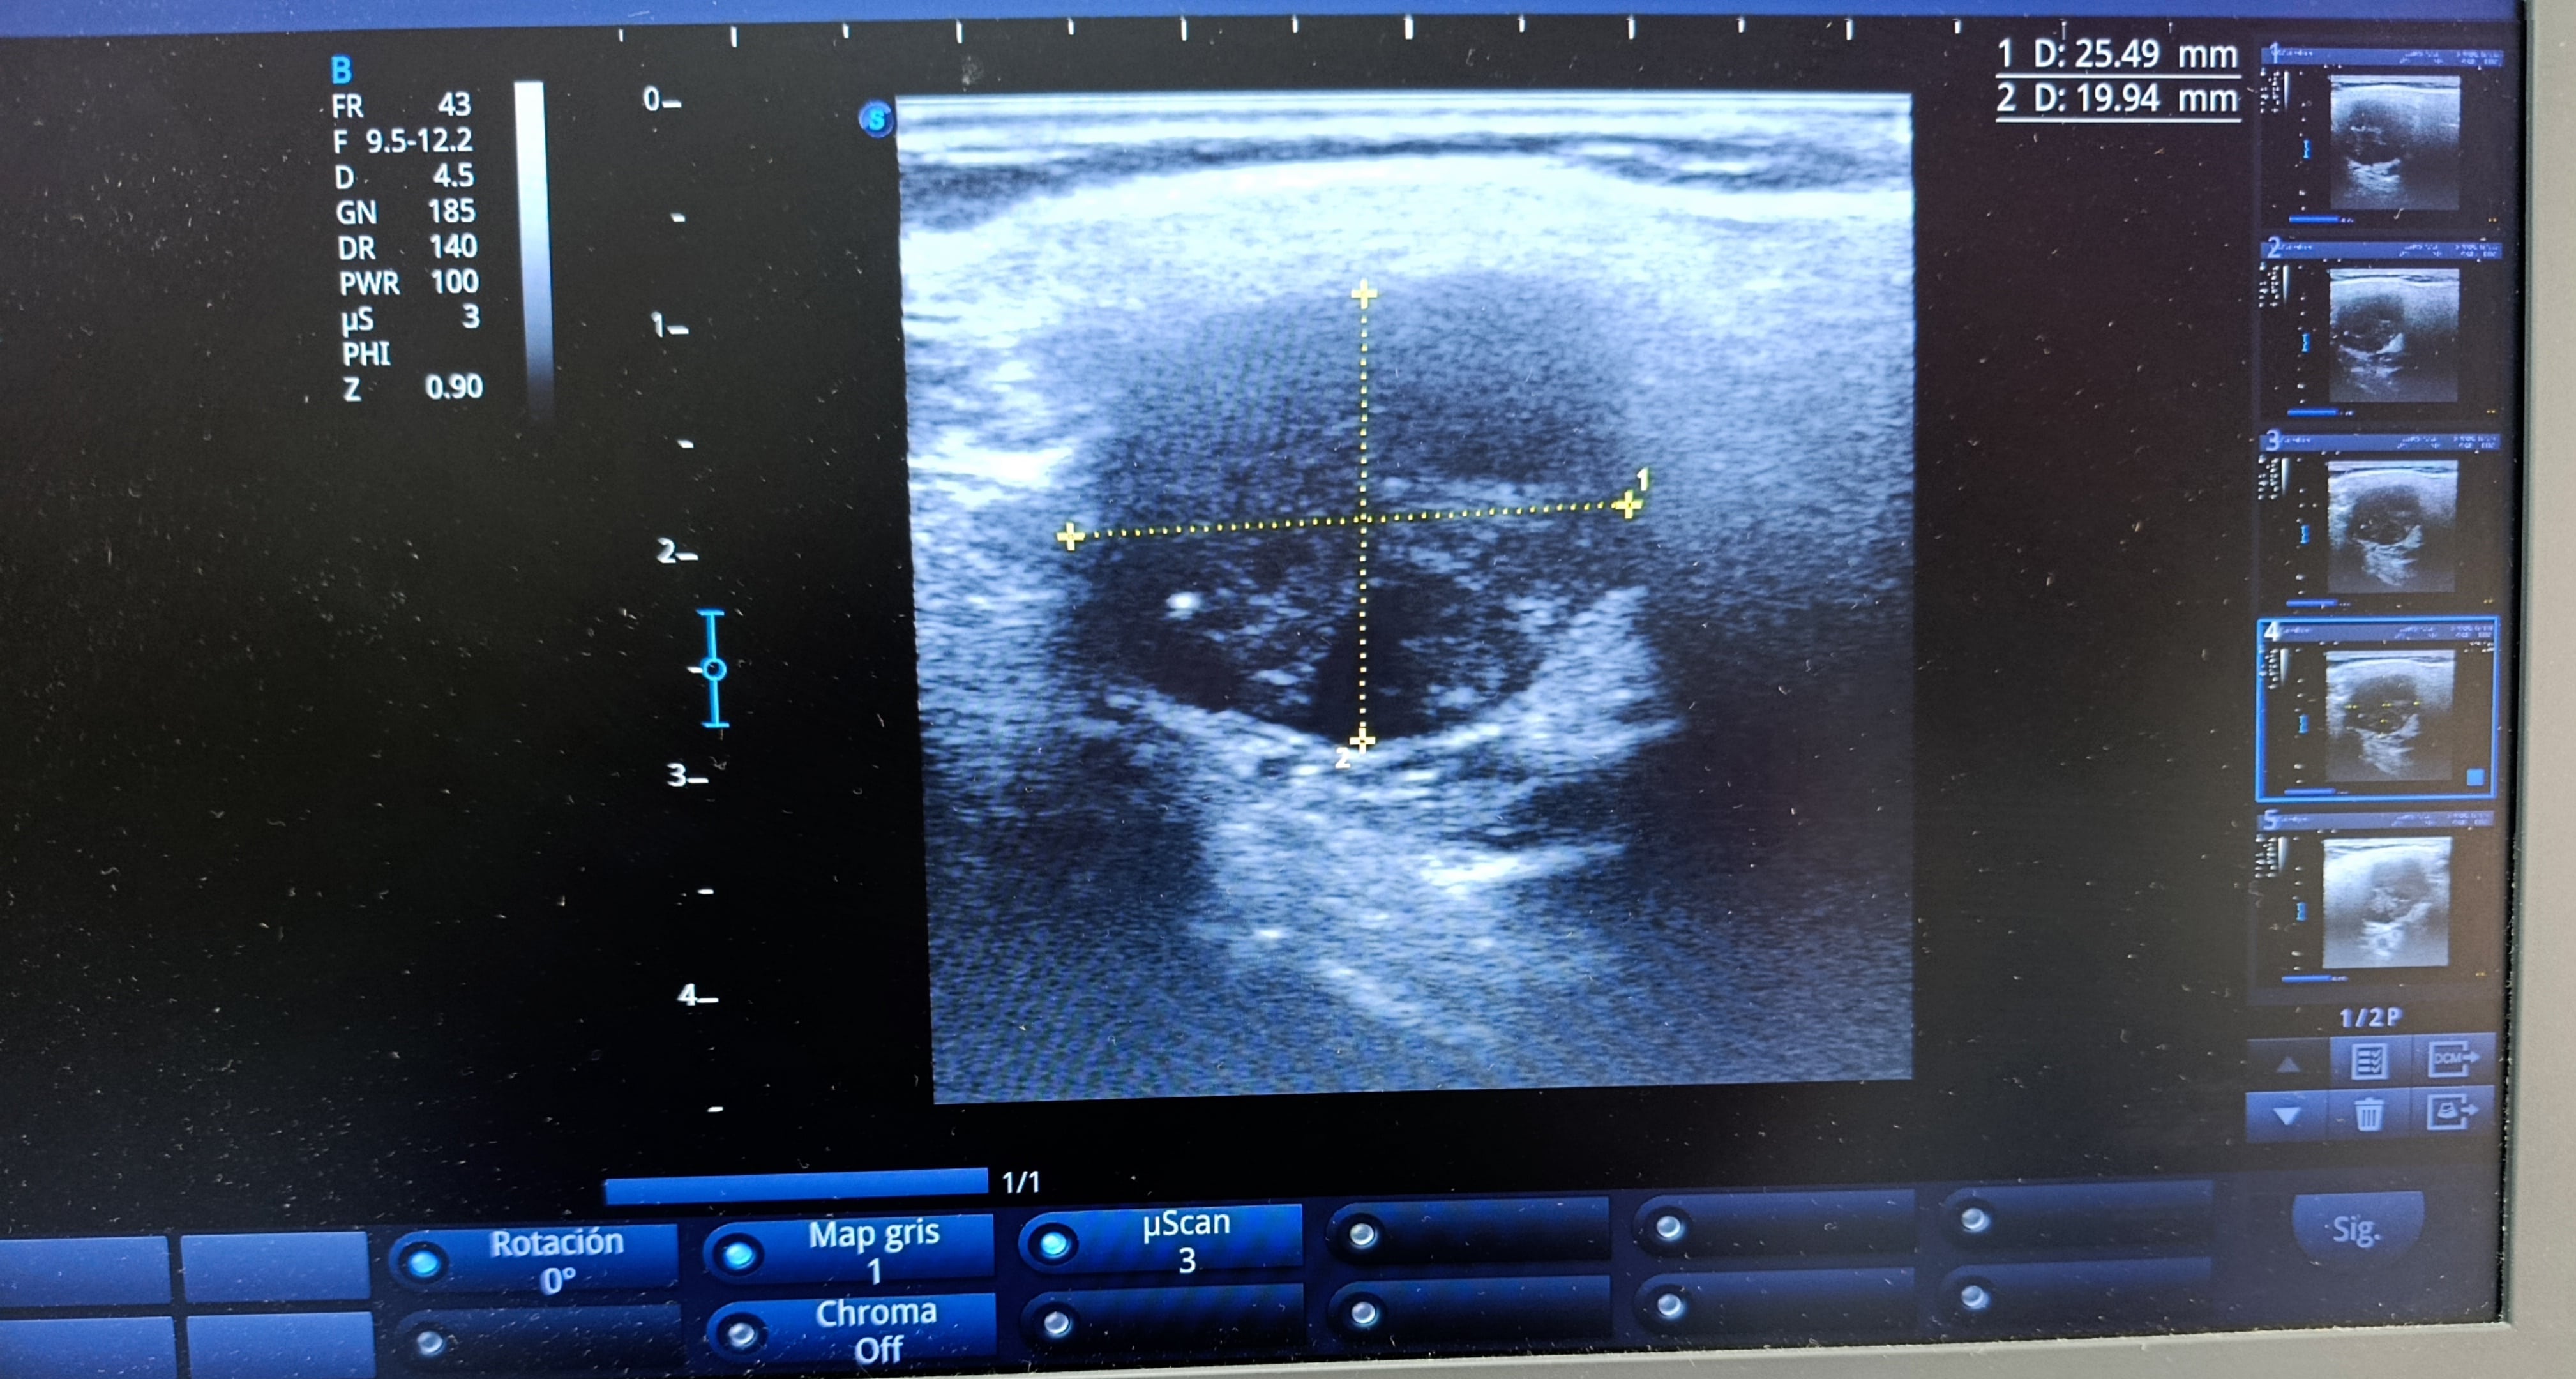

Realizamos ecografía clínica en consulta en región paratiroidea izquierda.

Hallazgos ecográficos

Ecografía clínica en consulta: lesión nodular de 29x19x22 mm de bordes regulares, ecogenicidad heterogénea con calcificaciones y zonas anecoicas en su interior, no hay captación Doppler. Realizamos derivación preferente a endocrinología.